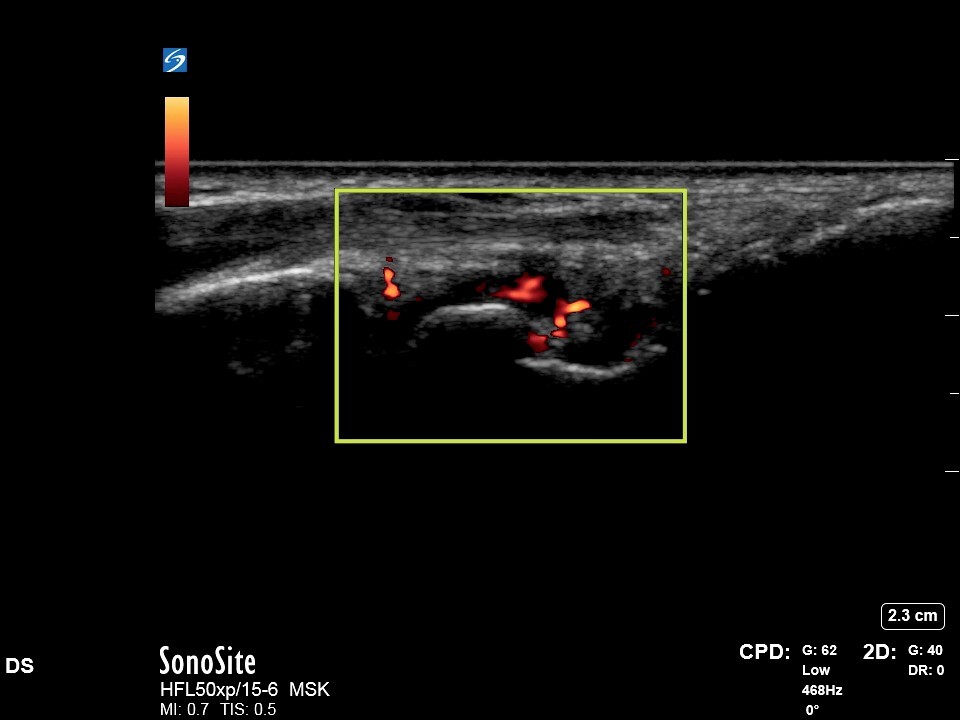

Wrist Dorsal Synovitis Abnormal Image